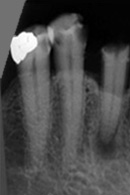

Dieser Zahn wurde schon geraume Zeit zuvor von einer Kollegin im Notdienst eröffnet und anschlies­send mit einer aufwendigen Amal­gamrestauration ästhetisch an­sprechend wieder verschlossen. (Bild 1) Uns blieb noch WK/WF, was bei massiver Überstopfung der hin­teren Wurzel auch gelang (Bild 2).

"Überstopfen ist immer noch besser als Unterstopfen" laut Koçkapan. OK, hier wurde des Guten aber ganz eindeutig zuviel getan.

Also direkt neben dem Zahn das Zahnfleisch ein wenig angehoben und zur Seite gedrängt und dann mit einem scharfen Löffel den Überschuss vollständig entfernt.

Schon 8 Monate später ist eine deutliche Verbesserung der Gesamt­situation unverkennbar (Bild 3). Verlorengegangene Knochensubstanz wurde in Teilen schon wieder aufge­baut, doch ist noch gar nichts entschieden. Schaun mer also ma'.

Abrechnungstechnisch hat der Mut zur WR an 38 gefehlt, deshalb nur EXZ1.